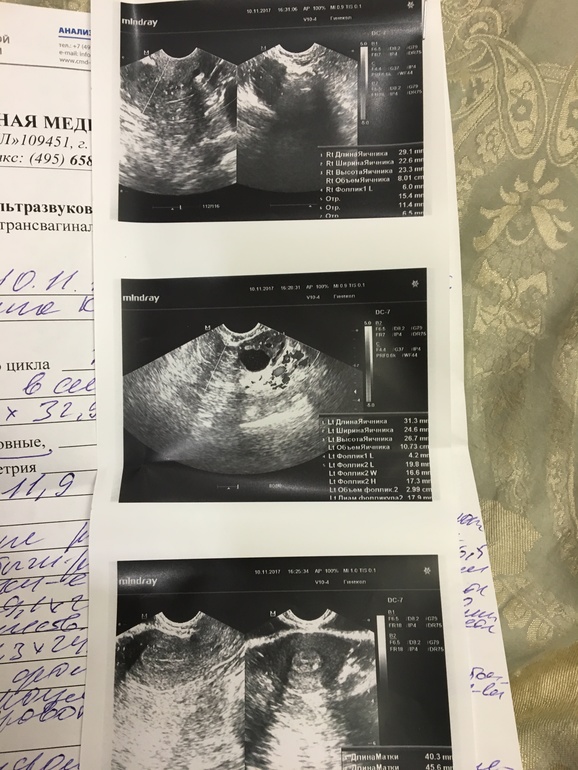

Девочки посмотрите на УЗИ, что скажете, шансы есть что беременность могла на ступить? Что о эндометрии скажете?